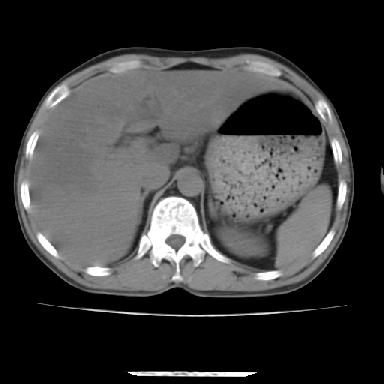

标题: CT7372:脂肪肝?外伤?

m 45 车祸,硬膜下血肿

窗宽太宽,调低点就好了,应该是不均质脂肪肝表现,请结合临床,单纯肝挫伤  其内无出血灶很少见,必要时做mri检查

窗宽太大,对比度太差了。局限性脂肪肝也有可能,但是亦不排除外伤性改变,增强扫描应该也还可以鉴别的。

肝内未见出血灶,但不能除外外伤性肝损伤,所示层面应考虑弥漫性脂肪肝.请结合临床必要时做mir检查

考虑不均匀性脂肪肝,建议增强扫描进一步检查除外合并其它病变。

肋骨无骨折,腹腔未见游离液体,所以不均匀脂肪肝首先考虑,但如果病人情况允许还是做个增强检查放心

考虑不均匀性脂肪肝,肝包膜下光整,肋骨无异常,无腹水征,不支持肝挫伤。